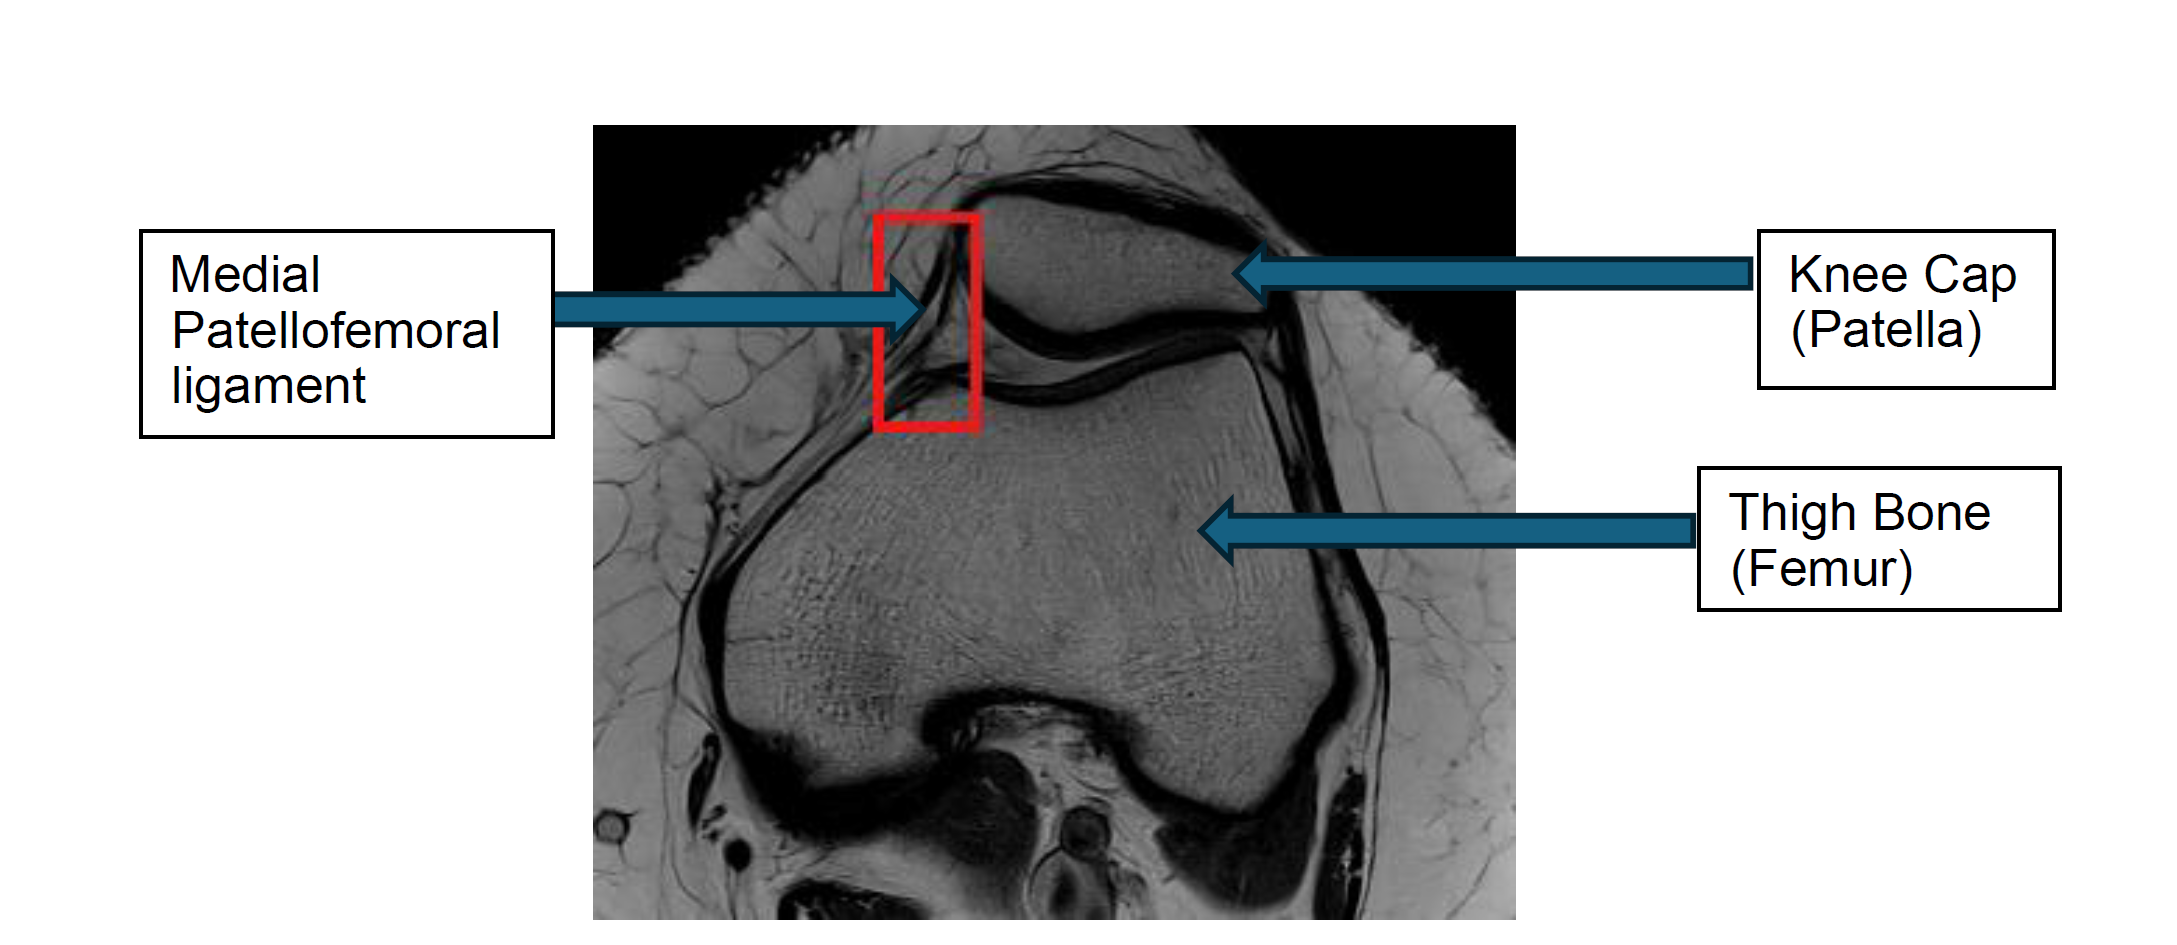

The Medial Patellofemoral Ligament (MPFL) is a band of tissue that connects the inner side of your kneecap (patella) to your thigh bone (femur).

It helps keep the kneecap stable and prevents it from sliding outwards. If the MPFL is torn or stretched, the kneecap may dislocate, causing pain, swelling, and instability.